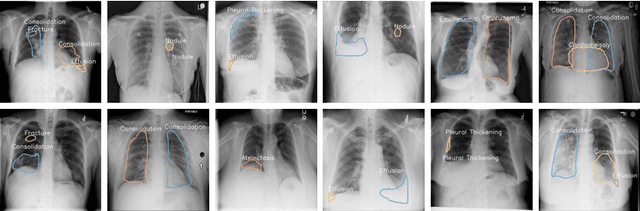

Abstract:Instance level detection and segmentation of thoracic diseases or abnormalities are crucial for automatic diagnosis in chest X-ray images. Leveraging on constant structure and disease relations extracted from domain knowledge, we propose a structure-aware relation network (SAR-Net) extending Mask R-CNN. The SAR-Net consists of three relation modules: 1. the anatomical structure relation module encoding spatial relations between diseases and anatomical parts. 2. the contextual relation module aggregating clues based on query-key pair of disease RoI and lung fields. 3. the disease relation module propagating co-occurrence and causal relations into disease proposals. Towards making a practical system, we also provide ChestX-Det, a chest X-Ray dataset with instance-level annotations (boxes and masks). ChestX-Det is a subset of the public dataset NIH ChestX-ray14. It contains ~3500 images of 13 common disease categories labeled by three board-certified radiologists. We evaluate our SAR-Net on it and another dataset DR-Private. Experimental results show that it can enhance the strong baseline of Mask R-CNN with significant improvements. The ChestX-Det is released at https://github.com/Deepwise-AILab/ChestX-Det-Dataset.